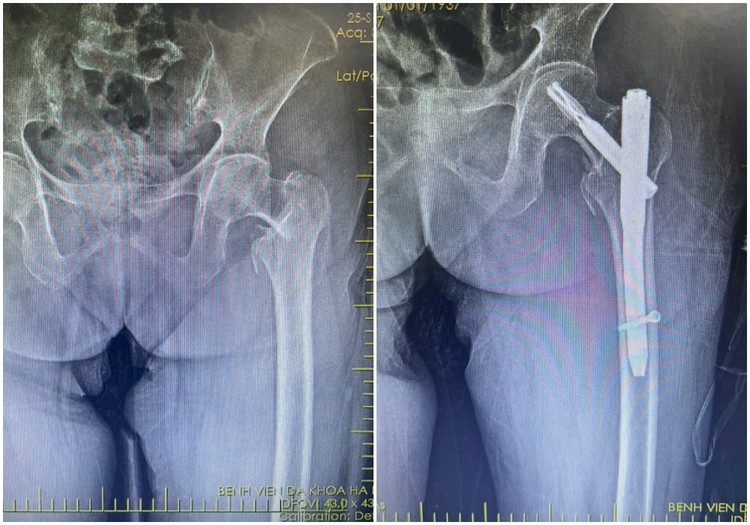

xuong-dui1.jpg

Hình ảnh X-quang gãy liên mấu chuyển xương đùi phải của bệnh nhân N (87 tuổi) được kíp mổ phẫu thuật kết hợp xương ít xâm lấn - Ảnh BVCC